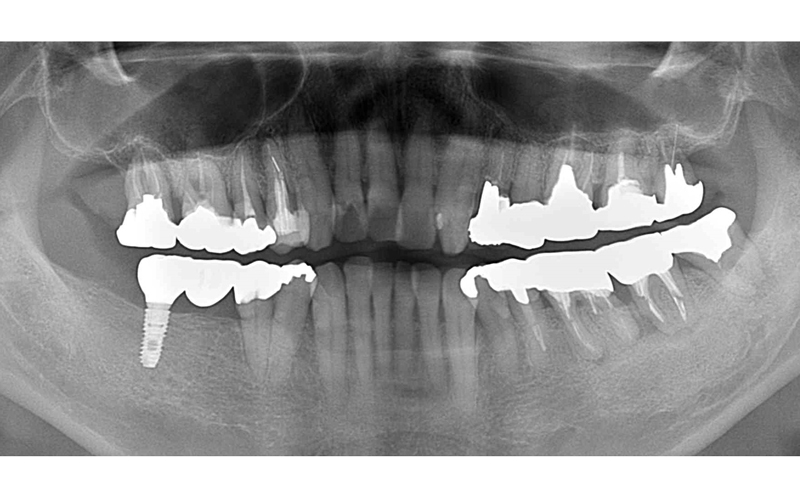

インプラント症例

Before

After

| 年齢・性別 | 59歳・男性 |

|---|---|

| 治療期間・回数 | 約7か月 |

| 治療方法 | インプラント埋入 上部構造 骨造成 |

| 費用 | インプラント埋入:200,000×5 上部構造:100,000×5 骨造成:30,000 合計:1,530,000円×Tax |

| 備考 | クロスバイトが所々あり、奥歯が崩壊しているのは咬合が強い方と思われました。 ナイトガードせず数年経過していますが、経過良好です。 |